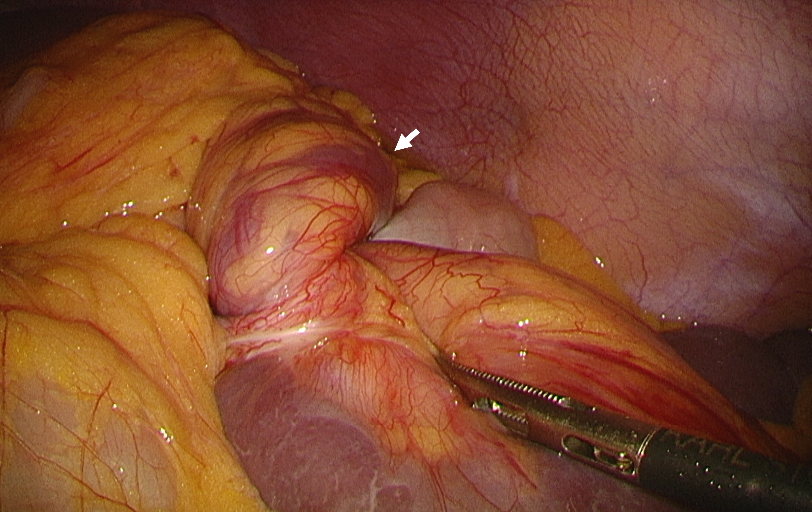

An abdominal CT was conducted and revealed splenomegaly and splenic infarction (Figure 2). Thus, a laparoscopic splenectomy was performed and spleen infarction due to splenic torsion was discovered (Figure 3). Antibiotic chemoprophylaxis and vaccination against Haemophilus influenza, meningococcus and pneumococcus were prescribed. The patient was discharged 5 days after the surgery without any complication.

Figure 2.

Figure 2.— Abdominal CT at the time of the second visit revealed splenomegaly and splenic infarction (arrow: whirl sign, asterisk: splenic infarction).

Figure 3.

Figure 3.— Wandering spleen was confirmed on laparoscopy. There was no adhesion to the surrounding structures and the spleen was found twisted three times around its vascular pedicle (arrow: twisted splenic pedicle).